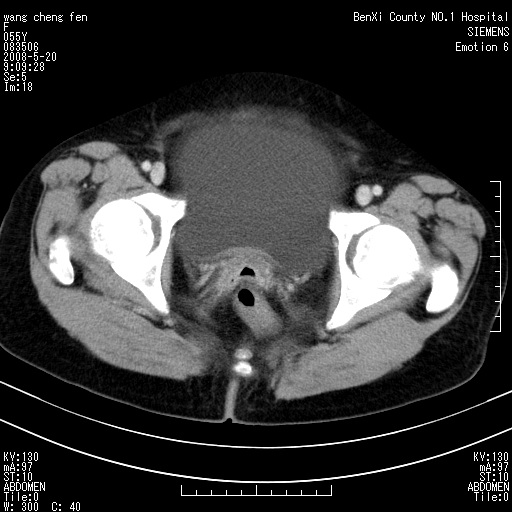

女、绝经后阴道流血3个月

左侧附件区可见一囊性占位,边缘清楚,内可见不规则形软组织影 ce:囊壁及内部可见强化 考虑 卵巢囊腺瘤

左侧附件区巨大囊实性病灶,边缘光整,病灶囊壁较厚,增强示囊壁及实性部分明显强化,强化呈度与宫体实质大致相同,宫腔积液征像,未见盆腔积液等其他异常,考虑左侧卵巢囊腺癌,不除外囊腺瘤及浆膜下肌瘤坏死

左侧附件区巨大囊实性病灶,边缘光整,病灶囊壁较厚,增强示囊壁及实性部分明显强化,强化呈度与宫体实质大致相同,宫腔积液征像,未见盆腔积液等其他异常。绝经后阴道流血3个月,结合病史左侧卵巢囊腺癌首先考虑,宫腔扩大不除外累及。期待结果。

支持浆膜下子宫肌瘤.之前由于网络原因未看全图片,现在重看,宫颈见一类圆形低密度影,增强轻度强化,低于肌层强化,宫腔扩大,考虑宫颈癌伴宫腔积液可能性大.